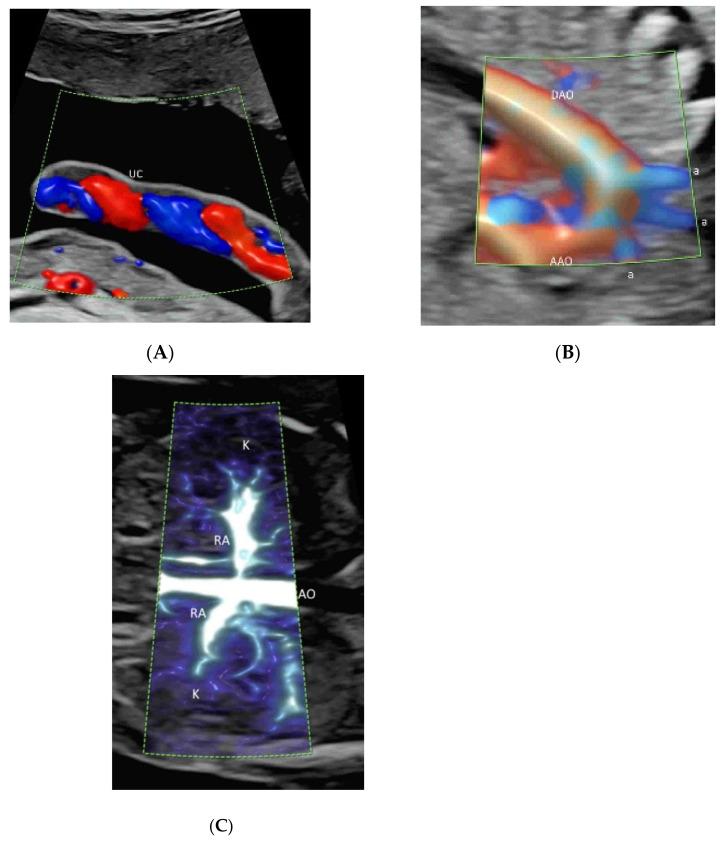

Color flow imaging (CFI), being non-invasive, is commonly used in obstetrics to study the fetal and placental circulations. The conventional CFI modes include color Doppler flow imaging (CDFI) and power Doppler imaging (PDI). In recent years, there is increasing use of new modes, including high-definition flow imaging (HDFI), radiant flow, microvascular flow imaging (MVFI), and three-/four-dimensional rendering in glass-body mode. Compared to CDFI, HDFI can show a higher resolution and sensitivity and allow the detection of slower flows. MVFI increases the sensitivity to fine or low-flow vessels while producing little or no motion artifacts. Radiant flow shows the blood flow with a sense of depth and reduces blood overflow. Glass-body mode, showing both gray-scale and color-flow information, can demonstrate the heart-cycle-related flow events and the vessel spatial relationship. In this review, the characteristics and applications of the various CFI modes in obstetrics are discussed. In particular, how these new technologies are integrated in detailed diagnostic and early morphology scans is presented.